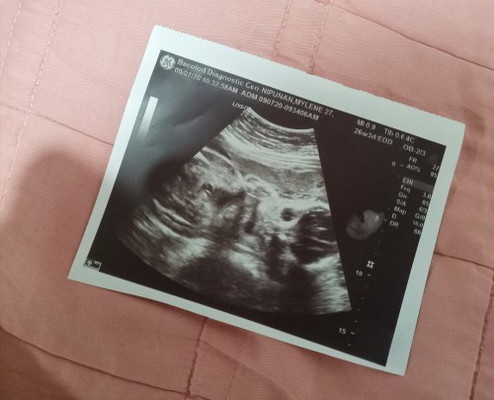

Possible kaya magka mali yung doctor na nag ultrasound sakin sa gender ng baby ko? Kası sabi niya una okay lg ba daw sakin hingi ako ng film ng ultrasound ko kung naka talikod at likod lg ng baby ko nakikita niya sa camera. Pero sabi pa niya babae daw anak ko. Pano nya yun makikita kung naka talikod sa camera? Tsaka nung lumabas ako hinintay ko ang film ng ultrasound ko, mukhang naka harap naman si baby. #firstbaby #1stimemom #advicepls #pregnancy #theasianparentph